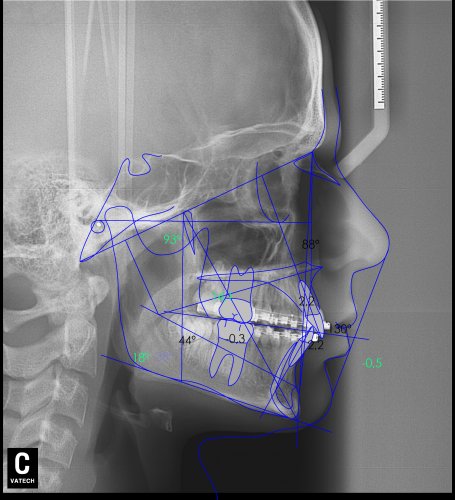

Paciente de 14 años, acude a nuestra consulta por dientes superiores proclinados hacia delante y apiñamiento. El paciente presenta una full clase 2, sobremordida y dientes inferiores proclinados. Decidimos colocarle brackets Damon y microtornillos en maxilar superior para distalizar las muelas. La duración del tratamiento fue de  24meses, y ahora lleva 1 año de contención. El paciente se pone la férula Essix superior 1noche/2 y la de abajo 1noche/semana para mantener.

Lateral Xray-1